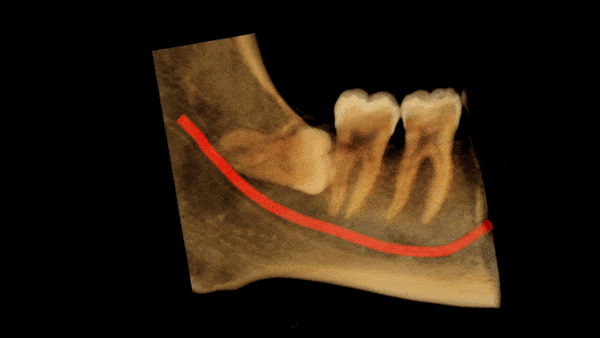

The LR8 is horizontally impacted, with two roots which appear to be fused. The inferior dental canal is narrowed and has a tight contact with the lingual surface of the apical half of the LR8 roots and then runs below the LR8 tooth. The canal is approximately 2.5mm below the mesial cemento-enamel junction of LR8. The findings indicate an intimate relationship between the canal and LR8.